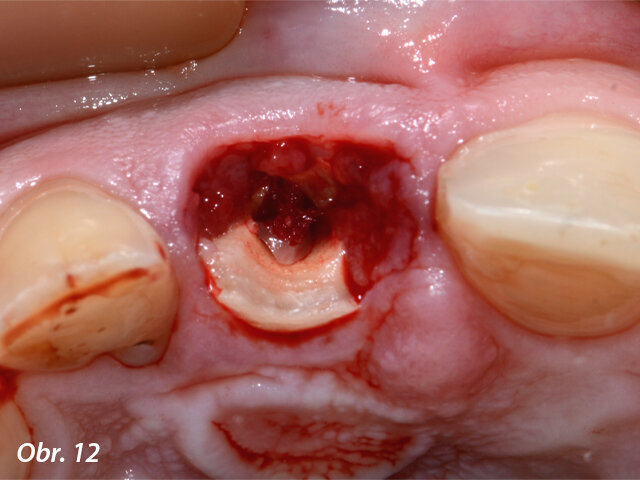

Viditelná granulační tkáň v místě resorpce a fraktury zubu 11.

Po atraumatické extrakci zubu 11 bylo možno díky laseru Fotona LightWalker důkladně očistit lůžko zubu od zánětlivé tkáně vzniklé vlivem chronického zánětlivého stavu. Dále byla provedena dezinfekce lůžka zubu laserem Nd:YAG. Implantát byl zaveden ve správné, předem naplánované, pozici s použitím chirurgické šablony vytištěné v Belgii ze speciální lékařské pryskyřice (s možností sterilizace výrobku před výkonem). Po sejmutí šablony byla našroubována korunka spolu s abutmentem (cementováno předem mimo ústa pacienta) do implantátu a dále byla provedena fotomodelace tkání laserem Nd:YAG s cílem získání lepšího a rychlejšího hojení. Kontrolní CBCT vyšetření ukázalo ideální lokalizaci implantátu vzhledem k plánované pozici.